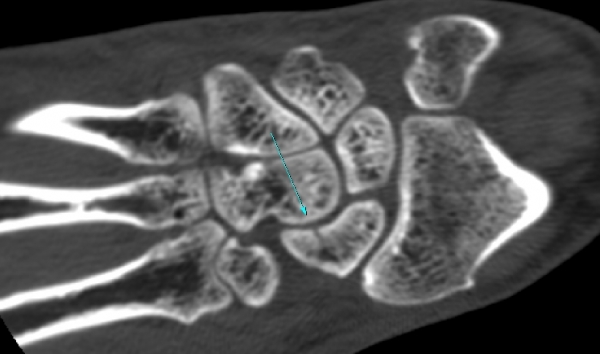

¼Õ¸ñ ¿ä°ñÃø ÁÖ»ó°ñ Á¾´Ü¸é °Ë»ç¿¡¼ ÁÖ»ó°ñ ÇÇÁú°ñ ¿¬¼Ó¼º ¼Ò½ÇÀÌ ¶Ñ·ÈÇÏ°í µ¿¹ÝµÈ ¿¬ºÎÁ¶Á÷ ºÎÁ¾ÀÌ °üÂûµÊ(»çÁø 3, 4)/

CT °Ë»ç